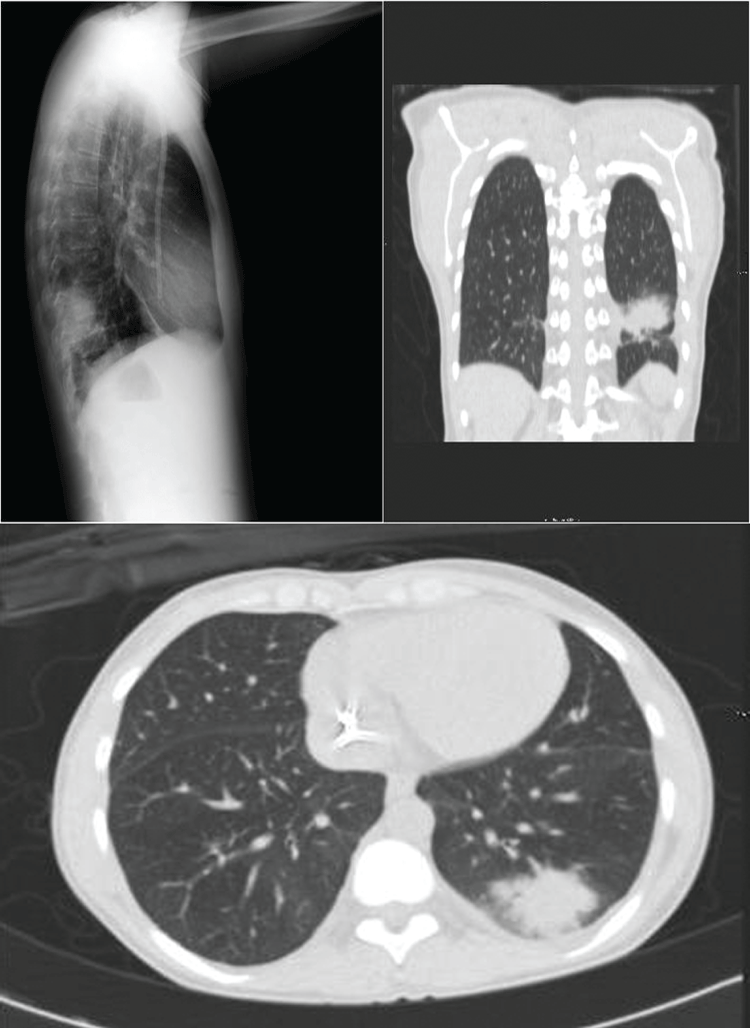

A 29-year-old woman with chronic kidney disease secondary to chronic interstitial nephropathy diagnosed by a kidney biopsy, in RRT with hemodialysis for 30 months using a right jugular tunneled catheter, began tacrolimus and prednisone treatment one week before hospital admission for a scheduled related kidney donor transplant. On admission, a simple chest X-ray showed a radiopaque image in the lower lobe of the left lung, confirmed by chest computerized tomography (CT) (Figure 1). An expanded study and empirical antibiotic treatment was decided in the absence of respiratory symptoms. Mycoplasma pneumoniae MIg was positive and Candida sp was detected in induced sputum after reviewing fluconazole and specific antibiotic treatment (the patient was discharged one month later). The kidney transplant (KT) was cancelled. CT was repeated six months later when the patient was asymptomatic. A reduction of the pseudo nodular consolidation in the posterior basal segment of the inferior lobe of the left lung (LIL) was observed, but with the presence of cavitated areas inside the consolidation. In addition, new ground-glass appearance injuries were detected in the right superior lobe (RSL), in the left superior lobe (LSL), the lingula and in both lung bases. Due to presence of fever and the radiological evidence the patient was readmitted for further study.

Figure 1: A) Chest computerized tomography (CT) showed radiopaque image in the lower lobe of the left lung; B) Chest computerized tomography (CT) showed ground-glass appearance injuries. View Figure 1